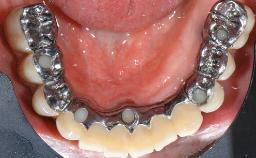

This case describes the ongoing management of a 64-year-old healthy, non-smoking female patient with erosive oral lichen planus (OLP) affecting the gingivae and the buccal and lingual mucosa. The peri-implant mucosa was also affected subsequent to implant placement. The patient had osseointegrated implants (four in the maxilla, four in the mandible) placed following extraction of hopeless teeth and a healing period. The patient had a history of OLP prior to implant placement and had been referred to an oral-medicine specialist for definitive diagnosis and treatment. She exhibited generalized oral mucosal involvement. Following a clinical assessment, biopsy, and blood tests, she was treated with topical corticosteroids. Systemic prednisolone was reserved for severe flare-ups. Amphotericin lozenges were used in combination with corticosteroid treatment to prevent the development of oral candidiasis.

# of Implants 8

Retention Screw-retained, with 4 or more splinted implants Screw-retained, with 4 or more splinted implants